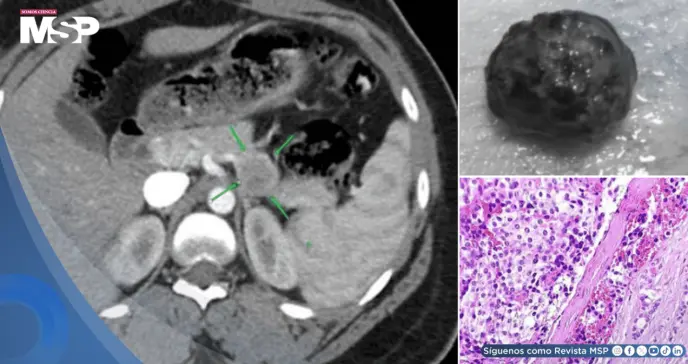

Para localizar la lesión, se realizó inicialmente una tomografía computarizada (TC) que identificó un tumor bien delimitado de 2.5 cm en la región cuerpo-cola del páncreas. Este hallazgo se corroboró con una ecografía endoscópica, y una citología por aspiración con aguja fina confirmó las características de un tumor neuroendocrino.

El análisis patológico del tumor resecado diagnosticó un tumor neuroendocrino bien diferenciado (Grado 1 de la OMS), de carácter benigno. Tras la cirugía, la paciente experimentó una resolución completa de todos sus síntomas.